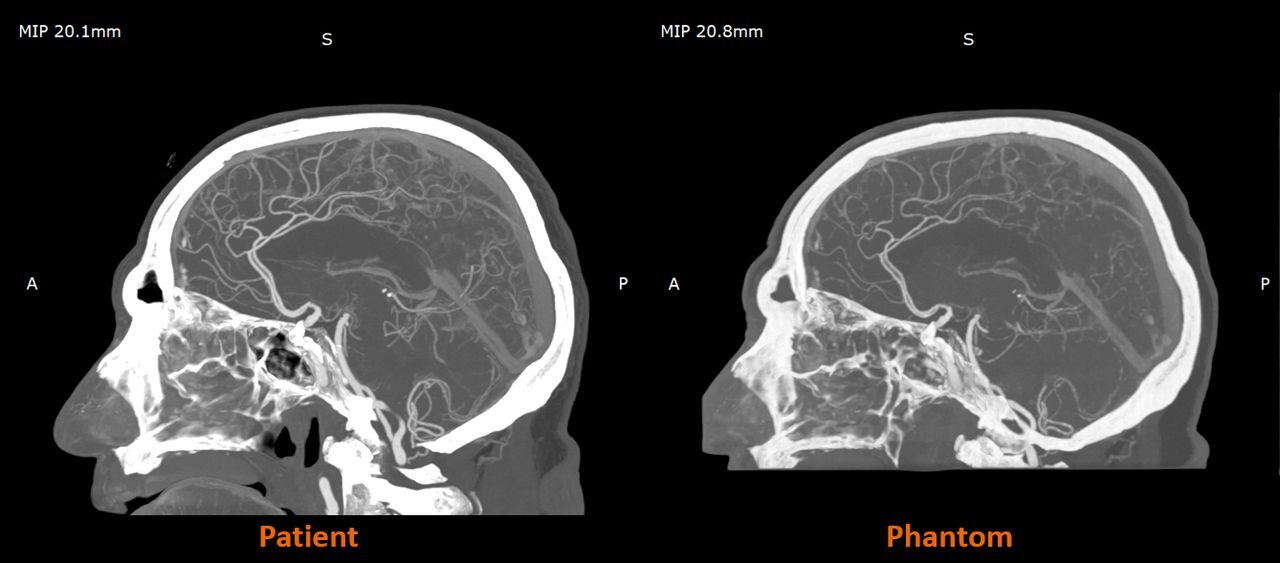

Stratasys Launches RadioMatrix Material to Enable Scannable 3D Printed Surgical Models

Stratasys announced general availability of a curious new material called “RadioMatrix”.